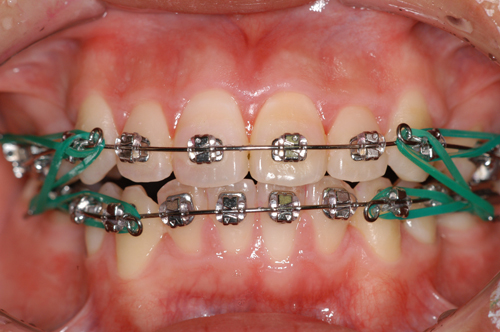

TIP-EDGE TECHNIQUE は以下の3段階のステップに別けて行われます。

1.叢生、捻転の除去

2.Overjet. Overbite の改善 |